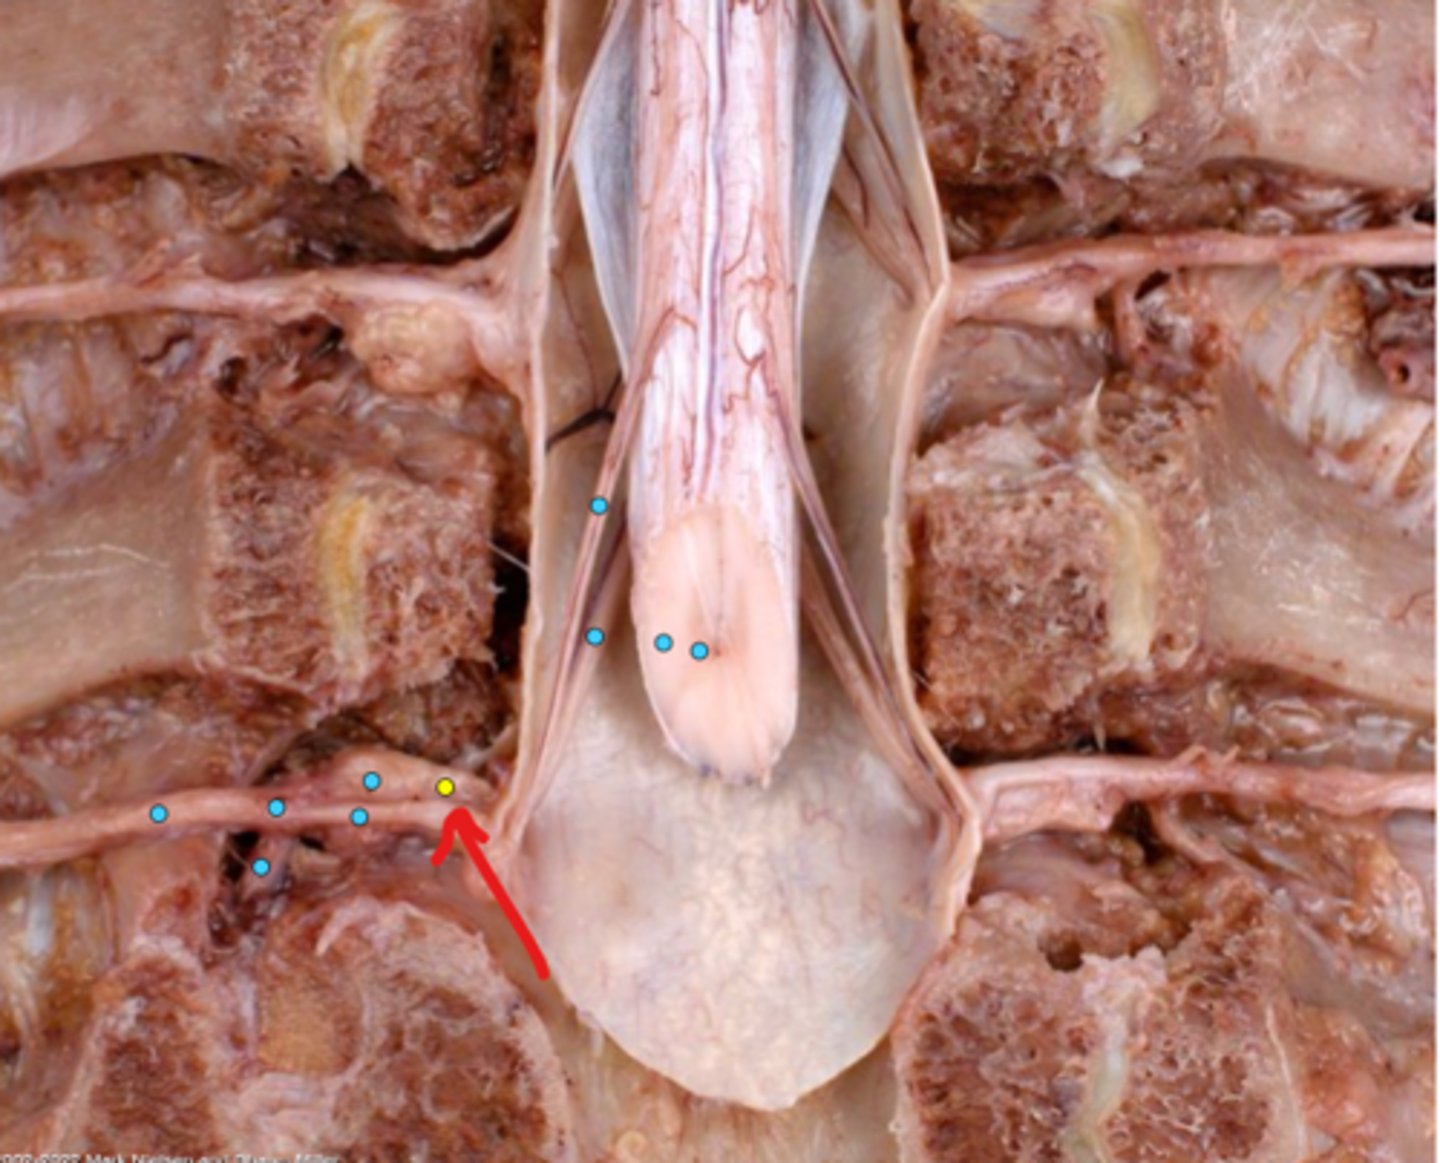

Intercostal nerve

Communicating ramus

Sympathetic trunk ganglion

Sympathetic trunk

Lesser splanchnic nerves

Greater splanchnic nerve

Anterior (ventral) ramus

Spinal nerve trunk

Posterior (dorsal) ramus

Spinal ganglion

Anterior (ventral) root

Posterior (dorsal) root

Anterior (ventral) rootlets

Posterior (dorsal) rootlets

White matter

Gray matter

Posterior (dorsal) rootlets

Anterior (ventral) rootlets

Spinal cord